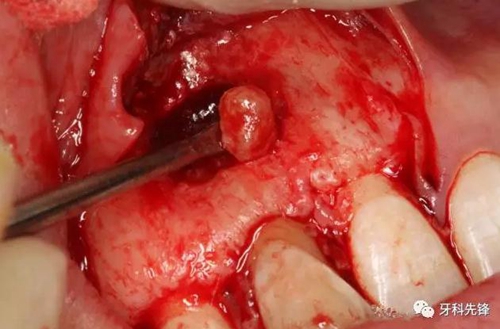

圖11.取出囊腔內(nèi)的致密團塊。

圖12. 取出沒有完全鈣化形成的牙齒。

圖13.摘除囊壁。